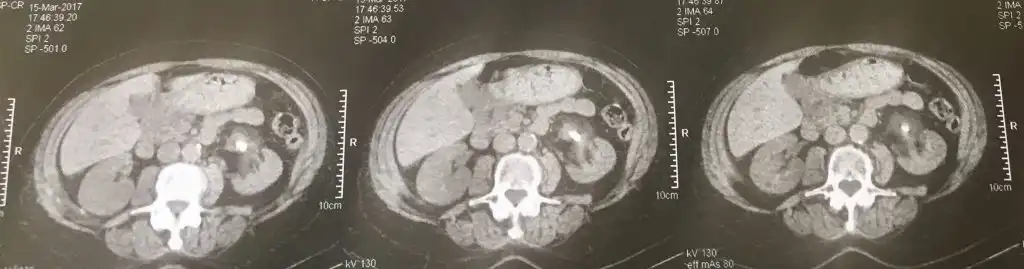

Ασθενής με φλεγμονώδη λίθο 3,2 εκ σε μέσο κάλυκα του αριστερού νεφρού αντιμετωπίστηκε με εύκαμπτη νεφρολιθοθρυψία με ψηφιακό εύκαμπτο ουρητηροσκόπιο μιας χρήσης της Boston Scientific ™. Η πρώτη φωτογραφία είναι προεγχειρητικά, ενώ η δεύτερη είναι στους 3 μήνες μετεγχειρητικά και αφού η ασθενής έλαβε συμπληρωματικά αγωγή για τη λιθίαση στρουβίτη.